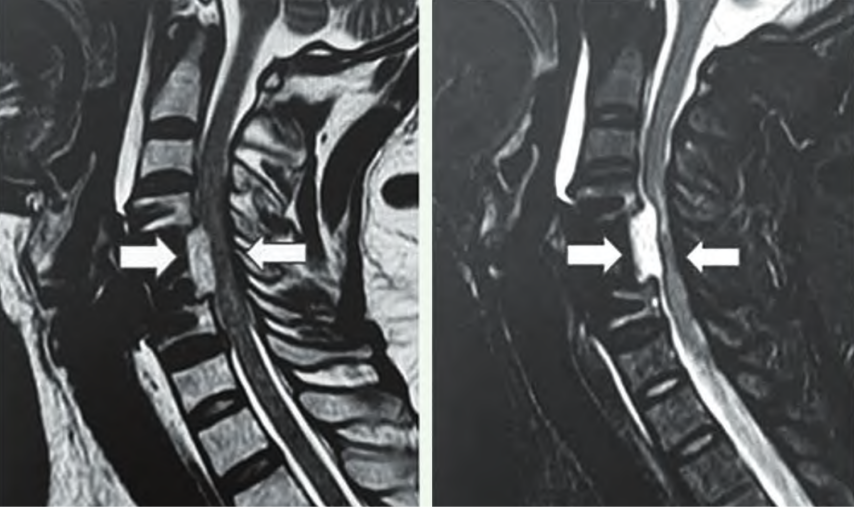

ACCF術(shu)后SEH示意(yi)圖(tu)

ACDF與ACCF術后均有(you)發生脊髓硬膜(mo)外血(xue)腫的可能,ACCF由(you)于創傷較大、滲血(xue)骨面較多而發生血(xue)腫風險較高(gao);但ACDF手術(shu)總體量(liang)更大,發生SEH的數量(liang)更多。